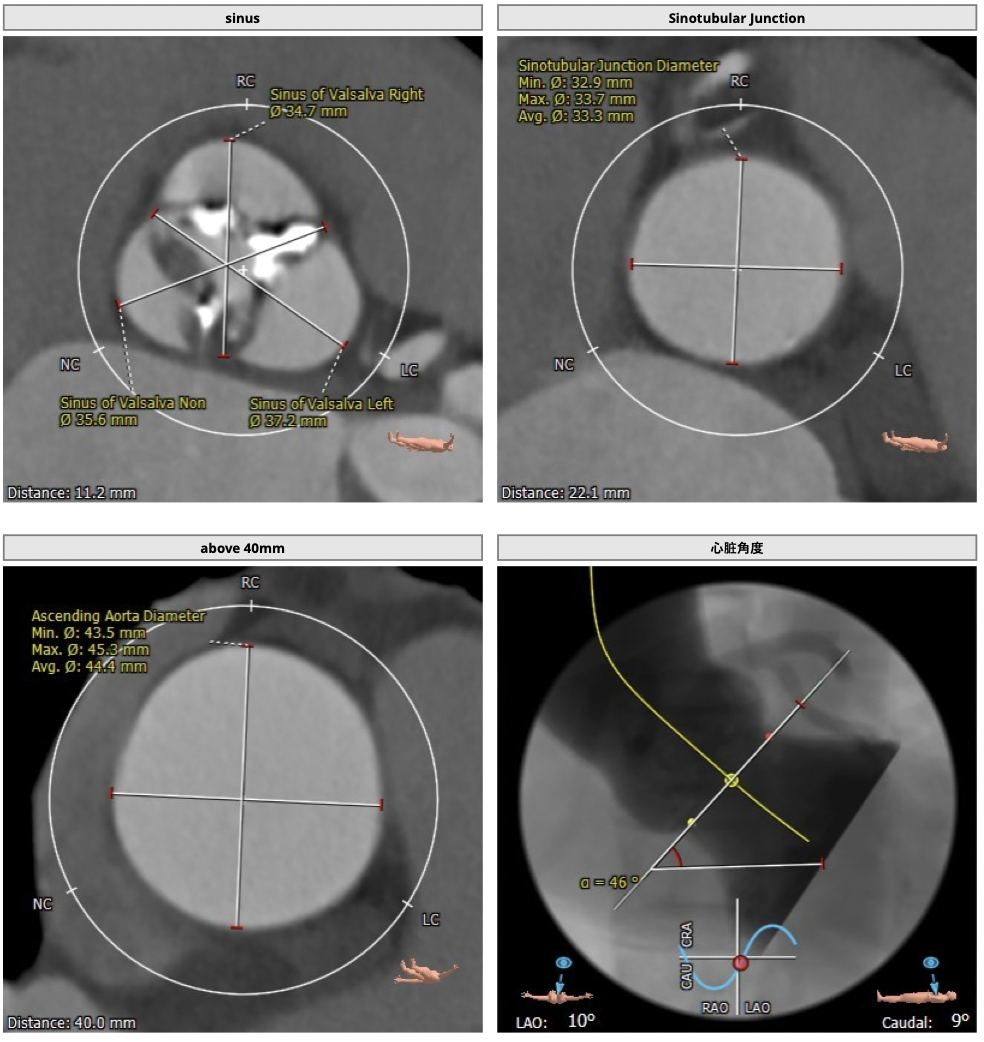

主动脉CT

图片

手术策略

CT分析:

*患者为TYPE1型二叶瓣,左右钙化融合,冠脉高度高,法式窦结构可,心脏角度约50°,左室大小可,心肌增厚,升主动脉未见明显增宽。主动脉弓部走形较平缓,右侧股动脉可作为主入路。

制定策略:

经分析研判,拟从右侧股动脉穿刺入路,使用23mm球囊预扩,选用L29号的VenusA-Valve瓣膜,采用VenusA-Plus可回收输送系统进一步确保手术安全,瓣膜释放后结合造影和超声情况,决定是否后扩。